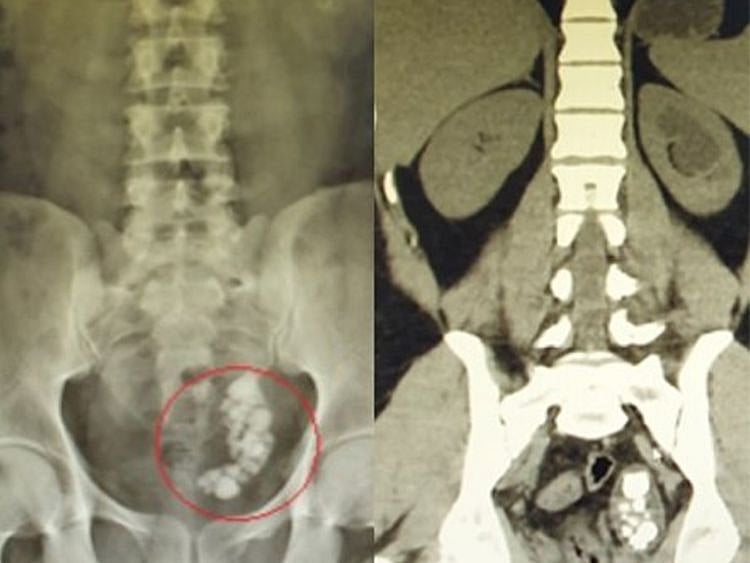

A detailed investigation, with an x-ray and an ultrasound, found that he had developed multiple stones blocking his ureter, ranging from eight to 22 millimetres in size.

Dr Hussain then opted to remove the stones by first breaking them with laser therapy.